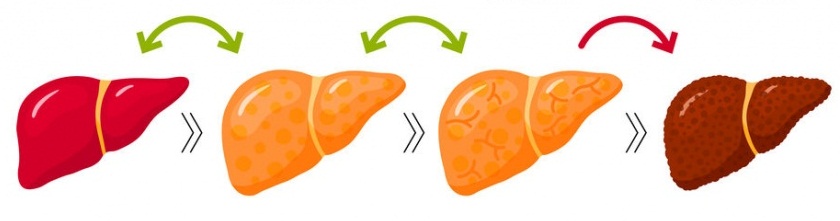

کبد چرب غیر الکلی (NAFL) مرحله اولیه و برگشت پذیر بیماری کبد است. متأسفانه، غالباً این بیماری تشخیص داده نمی شود. با گذشت زمان، کبد چرب غیر الکلی منجر به یک بیماری جدی تر کبد می شود که به عنوان استئاتوهپاتیت غیر الکلی یا NASH شناخته می شود.

استئاتوهپاتیت غیر الکلی شامل تجمع بیشتر چربی و التهاب است که به سلولهای کبدی آسیب می رساند. این بیماری منجر به فیبروز یا زخم بافت می شود، زیرا سلول های کبدی به طور مکرر آسیب دیده و از بین می روند.

متأسفانه، پیش بینی اینکه کبد چرب به استئاتوهپاتیت غیر الکلی تبدیل می شود یا خیر دشوار است. در واقع تبدیل کبد چرب به استئاتوهپاتیت غیر الکلی خطر ابتلا به سیروز کبدی (زخم شدید که عملکرد کبد را مختل می کند) و سرطان کبد را به شدت افزایش می دهد.

کبد چرب هنگامی ایجاد می شود که چربی زیادی در کبد تجمع می کند. کبد چرب در مراحل اولیه قابل برگشت است، اما گاهی اوقات به بیماری پیشرفته کبدی تبدیل می شود [1].